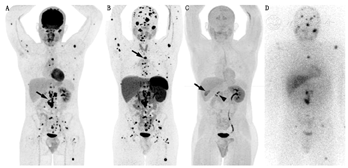

(2)临床效果。18F-FDOPA在PCC和(或)PGL显像中的应用见表1,表2。一项PCC和PGL的荟萃分析显示,18F-FDOPA PET/CT的灵敏度和特异性分别为91%和79%(基于患者)及95%和95%(基于病变)[31]。表1显示18F-FDOPA诊断良性PCC具有较高的灵敏度(85%~100%),优于MIBG。18F-FDOPA诊断良性PCC的灵敏度优于对良性交感神经PGL的灵敏度(94%与70%)[32];在非SDHx转移性PCC中,其检测转移性PCC灵敏度可达90%以上[23,33,34];尽管其他研究显示,其检测良性疾病的灵敏度为81%,检测恶性疾病的灵敏度为45%,但许多病灶可能被漏诊(图2)[11]。

18F-FDG在检测转移性病变方面常优于MIBG[33,39],高达90%的MIBG阴性病变18F-FDG显像呈阳性(图2)[15]。在转移性PCC和PGL中,18F-FDG的灵敏度为51%~100%,通常超过80%[11,14,15,24,39,40]。这种较大的差异可能与纳入患者群体特征不同、是否存在特定基因突变,以及采用的"金标准"有所差异有关(表2)。在一项前瞻性研究中,Timmers等[24]首次报告了18F-FDG显像在SDHB突变患者中的优势,其对区域转移灶的灵敏度为97%,而123I-MIBG为65%,111In-喷曲肽为50%,骨显像为83%。随后的研究证实,18F-FDG在SDHx患者中的灵敏度为79.4%~100%[11,13,20,41,42,43,44]。因此,18F-FDG是转移性病变、尤其是SDHx肿瘤患者的首选显像方式,灵敏度为83%~92%,而对非SDHx肿瘤的灵敏度为62%[11,42]。然而,正如接下来所讨论的,该建议是在68Ga-DOTA-SSA评估前提出的。

在一项对22例散发性转移性PCC或PGL患者的前瞻性研究中,68Ga-DOTATATE检出98%的转移灶,优于18F-FDG(49.2%)、18F-FDOPA(74.8%)和CT/MRI(81.6%)[34]。在具有SDHx突变的患者中,68Ga-DOTATATE基于病灶的灵敏度高于18F-FDG(图2)或CT/MRI[13,43,44]。总体来说,68Ga-DOTATATE应被视为评估转移性PCC、转移性PGL、SDHx突变和HNPGL的首选显像剂。但对于红细胞增多症相关、MAX突变相关的PCC或PGL,或明显散发性PCC,18F-FDOPA可能是首选。针对评估SSA在良性PCC中应用的研究有限。在一项纳入32例患者的研究中,111In-喷曲肽的灵敏度为25%[54],而68Ga-DOTA-SSA的灵敏度预期更高,18F-FDOPA仍是首选显像剂。